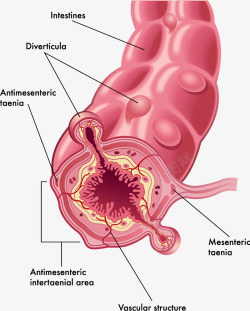

人体大肠结构分析图